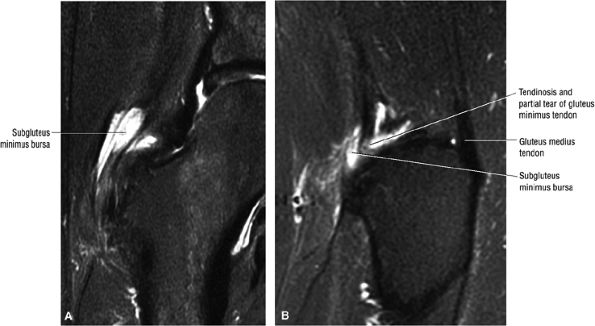

FIGURE 3.16 ● GLUTEUS MEDIUS The gluteus medius abducts and medially rotates the thigh when the extremity is extended.

FIGURE 3.17 ● GLUTEUS MINUMUS The gluteus minimus abducts and medially rotates the thigh when the extremity is extended.